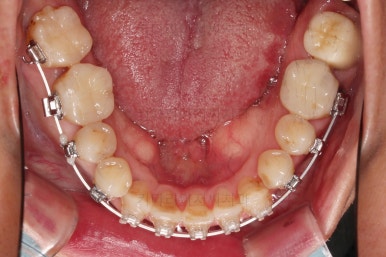

위아래 장치를 부착했습니다.

초기 단계의 주안점은 아랫니와 악궁과 어울리는 윗니 악궁의 형태를 만들어 주는 것이고요.

악궁확장장치를 사용하지 않은만큼 철사의 형태를 잘 잡아가면서 악궁 형태를 개선시킵니다.

교정 10개월째인데, 악궁형태 많이 좋아졌고, 가지런한 느낌도 많이 좋아졌습니다.